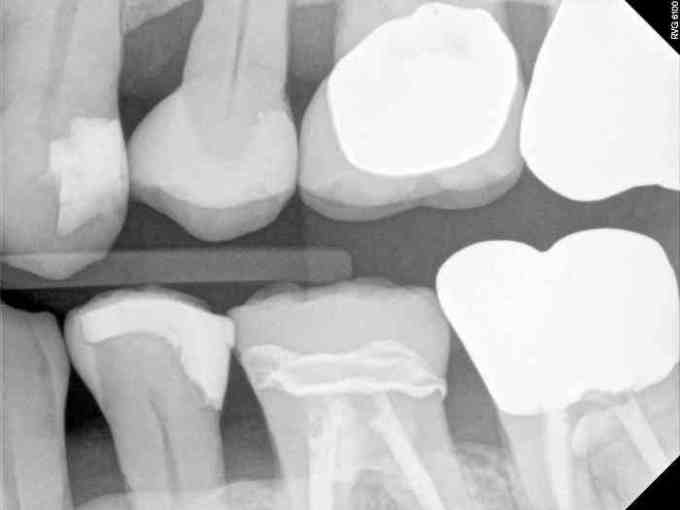

Question 10: Which option can be selected for the following X ray?

Question 11: Which materials cannot be seen in the print of the X ray?

Question 12: What option cannot be selected for the following X ray?

Question 13: What option cannot be selected for the following X ray?

Question 14: Which surface shows overhang restoration?

Question 15: Which surface shows overhang in the restoration?